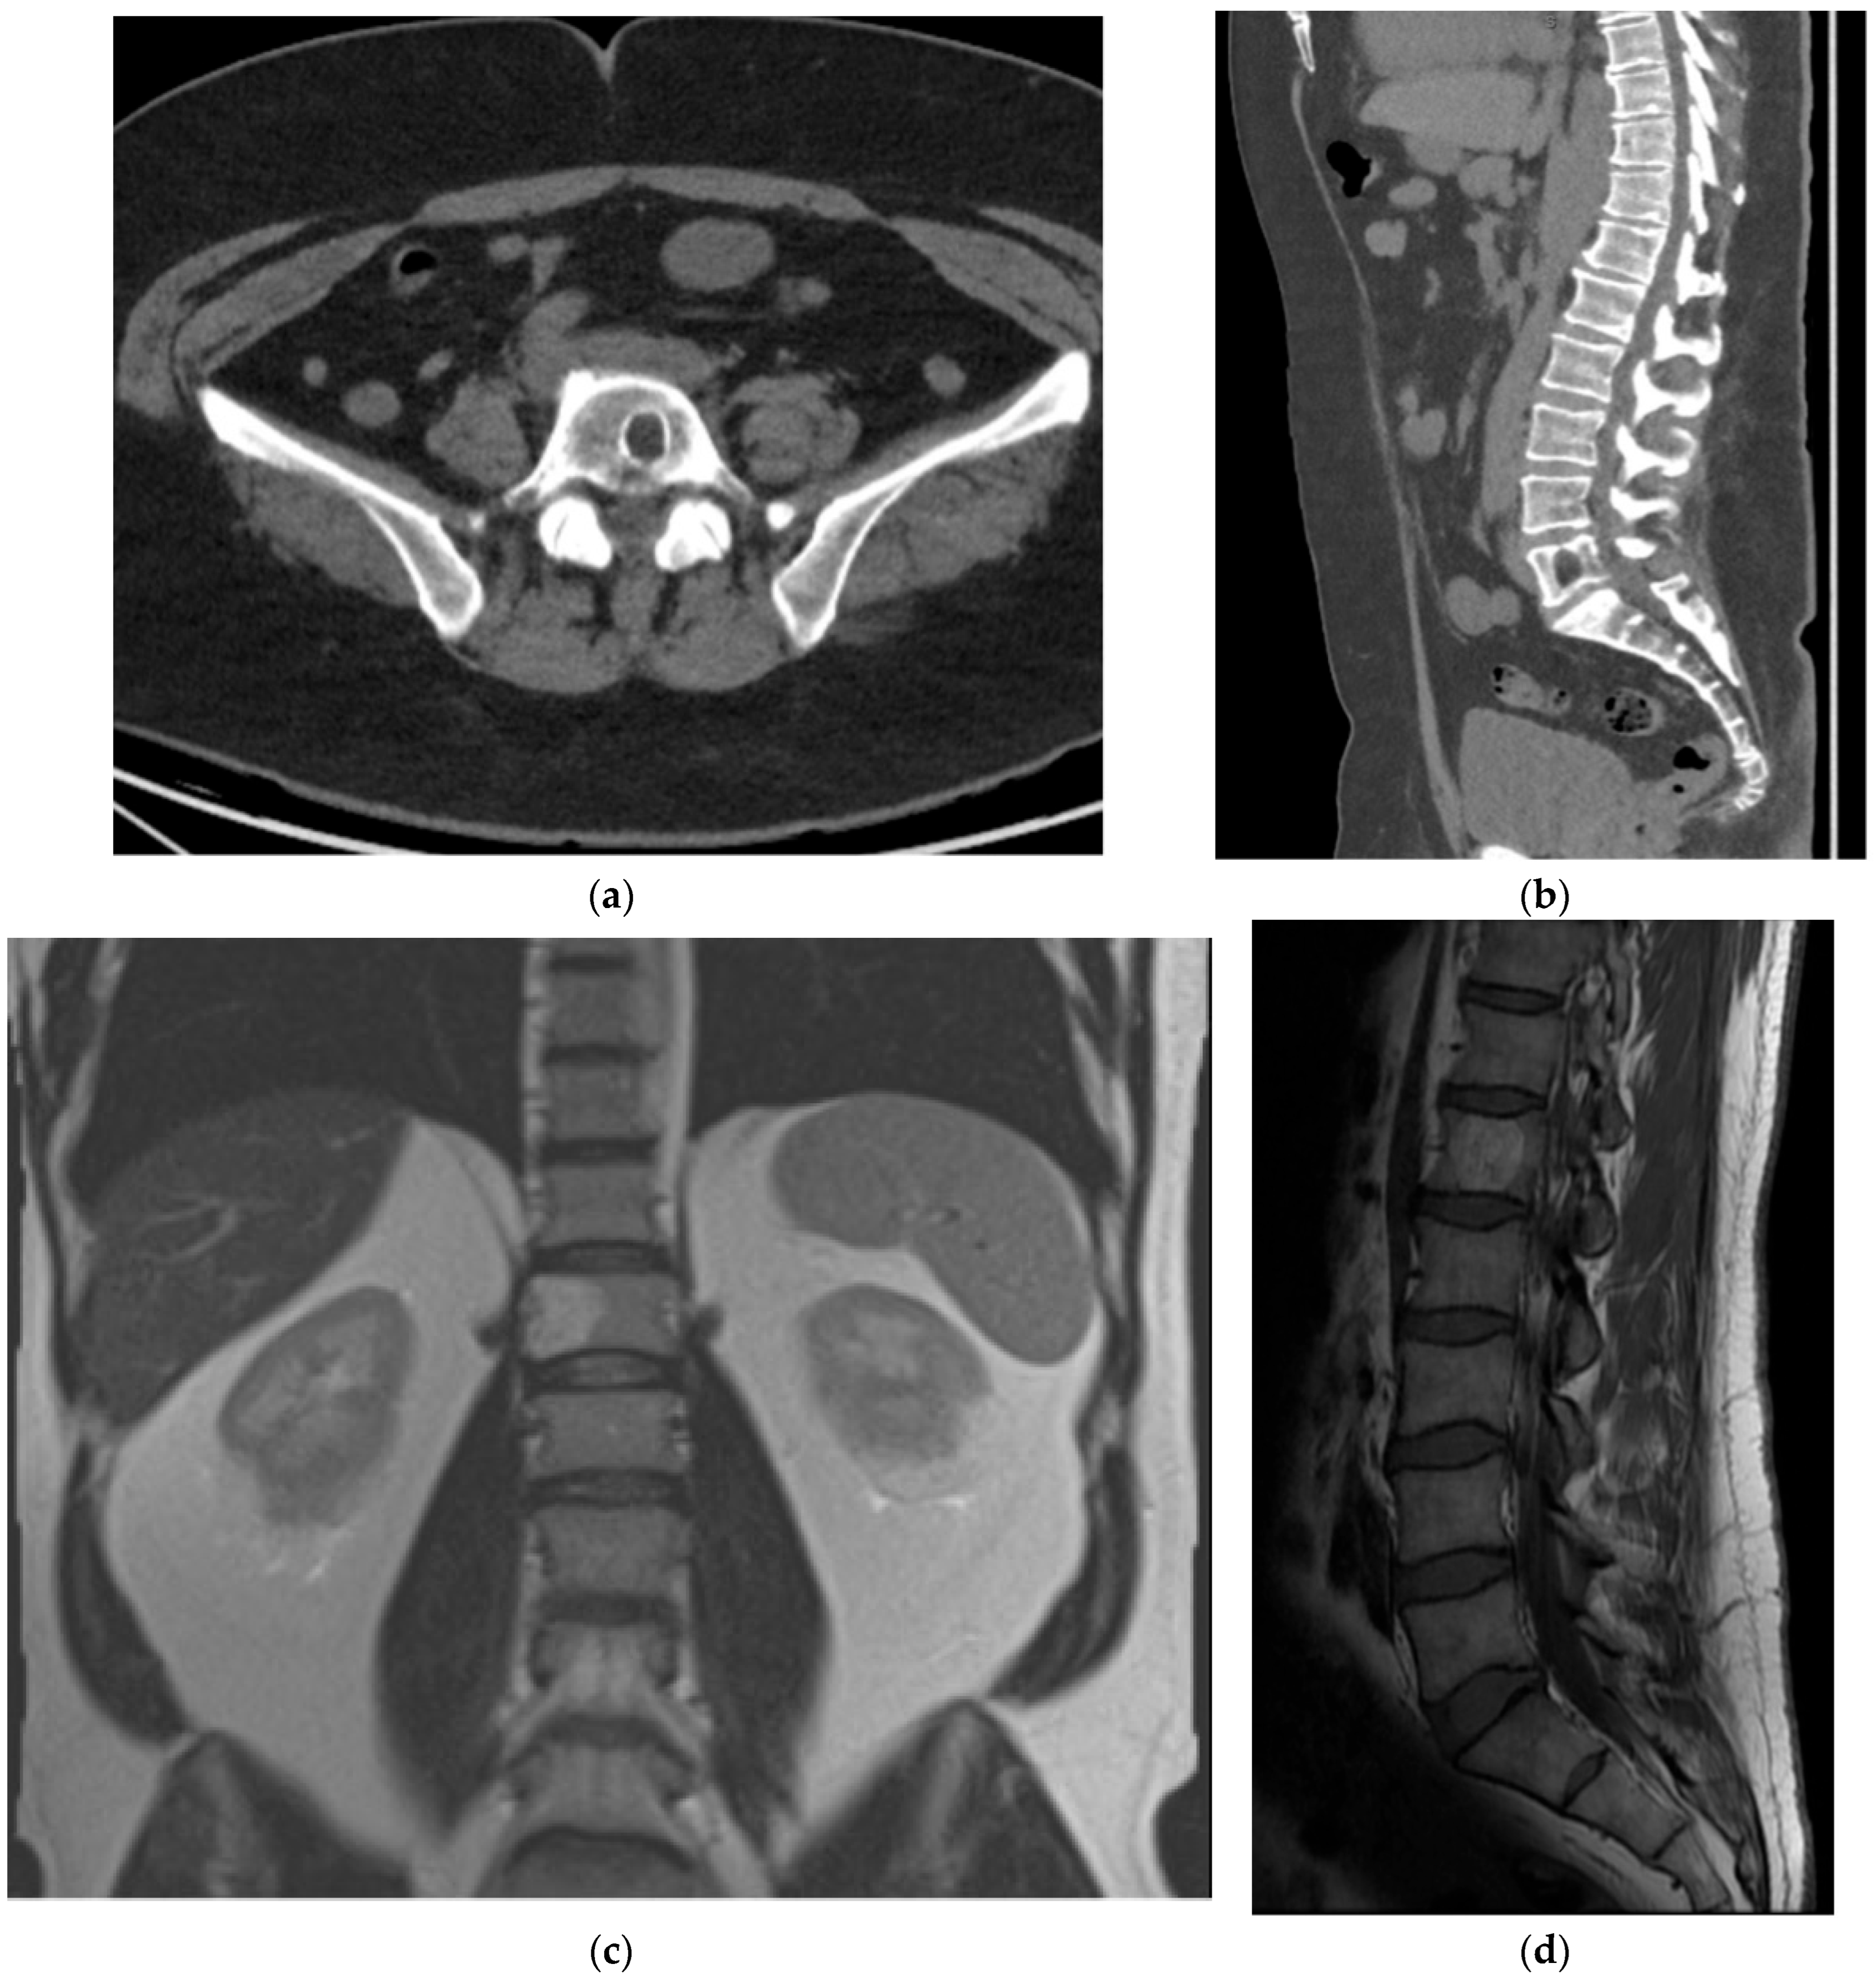

2.3. Notochordal

2.3.2. Chordoma

2.4. Hematolymphoid